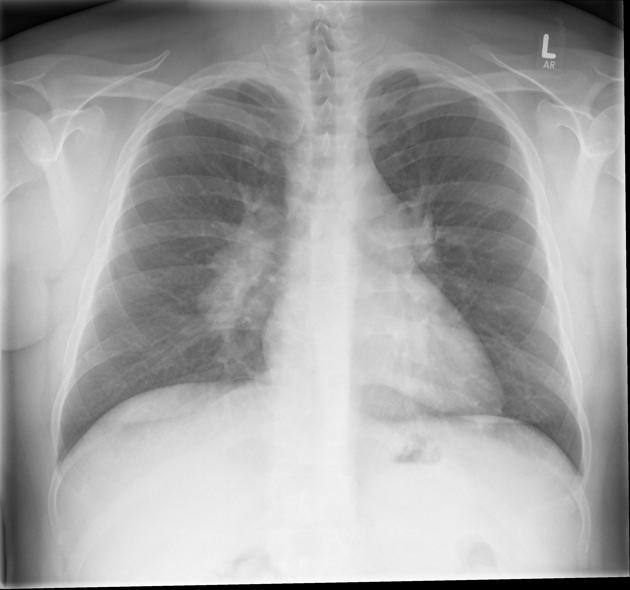

Stages of Pulmonary Sarcoidosis (Chest Imaging)

Pulmonary sarcoidosis is often classified into stages based on chest X-ray findings (not disease severity):

- Stage 0: Normal chest X-ray

- Stage I: Enlarged lymph nodes in the chest (hilar adenopathy)

- Stage II: Lymph node enlargement + lung infiltrates

- Stage III: Lung infiltrates without lymph node enlargement

- Stage IV: Pulmonary fibrosis (permanent lung scarring)

Not everyone progresses through all stages, and many people improve or go into remission.

- Chest X-ray